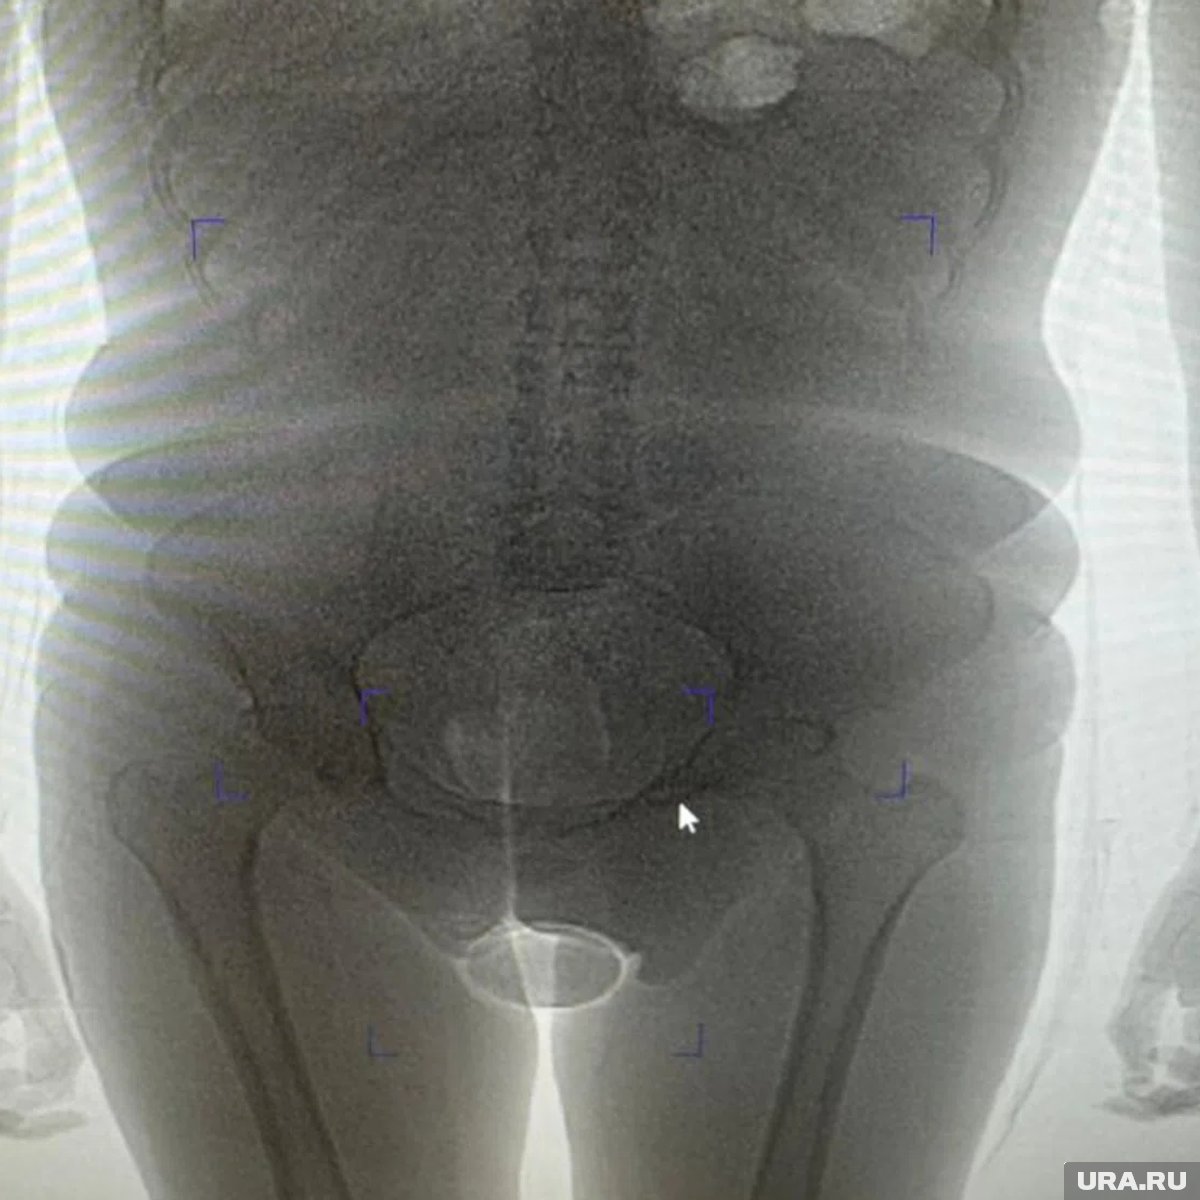

Сотрудники таможенного поста аэропорта Домодедово задержали гражданку Бразилии, подозреваемую в попытке незаконного ввоза наркотиков внутриполостным способом. По данным ведомства, 22-летняя пассажирка, прибывшая рейсом из Дубая, была остановлена в «зеленом» коридоре в рамках проведения оперативно-разыскных мероприятий. Об этом для URA.RU сообщила пресс-секретарь Домодедовской таможни Елена Мартынова.

«В результате проведения таможенного досмотра обнаружено два презерватива с порошкообразным веществом внутри, один из которых находился в нижнем белье пассажирки, второй сокрыт внутриполостным способом», — говорится в заявлении пресс-секретаря. Информация есть в распоряжении URA.RU.